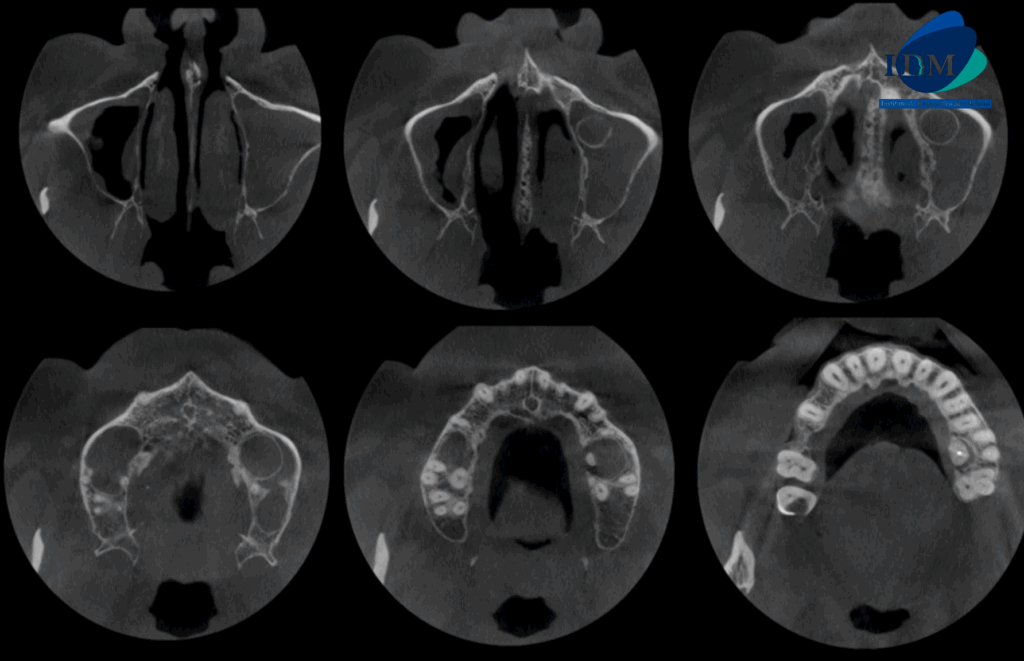

A la evaluación de la tomografía computarizada en cortes axiales, transaxiales y tangenciales se observa la pieza 16 con la raíz mesiovestibular con una obturación parcial y sobre extendida del conducto, asimismo presenta un conducto colateral obliterado y un proceso osteolítico periapical y reabsorción radicular externa del tercio apical; la raíz distovestibular presenta también una obturación parcial de conducto y la raíz palatina presenta un espigo intrarradicular, obturación parcial y subextendida del conducto y una imagen hipodensa corticalizada que desplaza hacia cefálico el piso de seno maxilar y compromete la tabla ósea palatina compatible con quiste radicular, asimismo ocasiona un engrosamiento de la mucosa antral ipsilateral compatible con sinusitis de origen odontogénico.

CORTES AXIALES